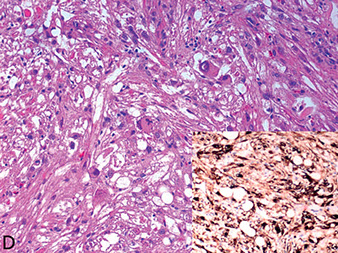

Xanthogranulomatous pyelonephritis

Staghorn calculus, E. coli, Proteus

- the result of suppurative sequela of chronic pyelonephritis

Gross: yellow-grey parenchyma tissue around dilated calyces and pelvices (2/2 staghorn calculi)

Micro: lots of foamy histiocytes c mixed inflam and some MNGCs

- 3 "zones":

Inner zone: neutros, lymphs, plasma cells, histiocytes c lots of necrosis and cholesterol

Middle zone: lymphos and granulation tissue

Outer zone: foamy histiocytes

DDx: clear cell RCC and malakoplakia